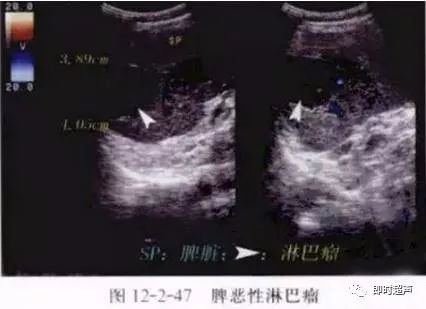

(3)脾恶性淋巴瘤超声图像特征:脾脏增大,形态失常。肿瘤呈单发或多发的类圆形低回声区,边界清晰,边缘整齐。病灶<1cm时可呈弥漫性点状低回声。彩色多普勒超声表现为瘤内及周边血流色彩丰富,呈搏动性动脉血供,脉冲多普勒显示脾门区动、静脉血流速度及血流量明显增大。

图5、6脾恶性淋巴瘤超声图